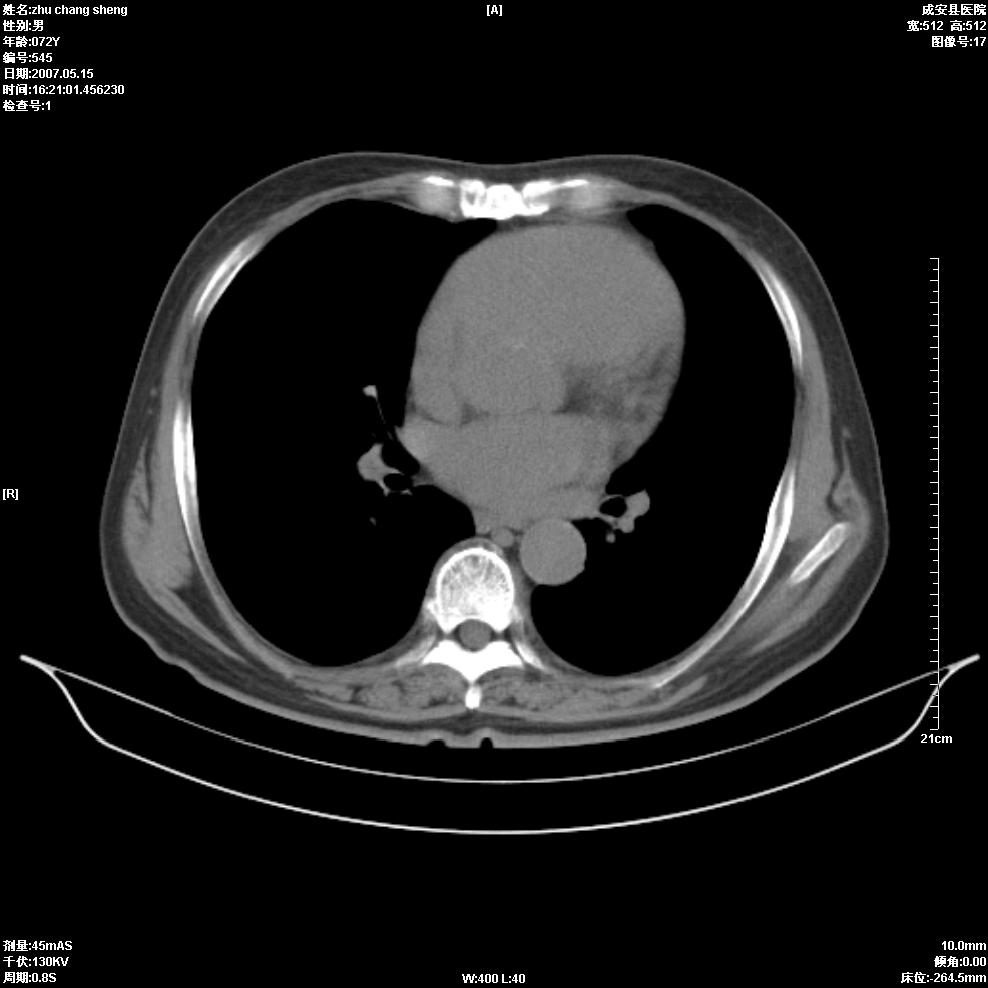

以下是引用医博云天在2007-5-15 19:10:00的发言:[br]心包积液,胸腔积液,心影增大,左心为主。

以下是引用zhangzhongshou在2007-5-15 20:21:00的发言:[br]心包积液可以肯定有,肿块显示不清,建议增强或mri检查。

以下是引用jinning在2007-5-15 21:06:00的发言:[br]心包积液可以肯定,建议增强或mri检查吧!

以下是引用拾荒者在2007-5-15 22:28:00的发言:[br]心包膜增厚,有少量积液,右室前壁示均匀软组织密度影,边界欠清,建议增强扫描或mri检查与室壁瘤鉴别。

以下是引用还珠格格在2007-5-19 9:50:00的发言:[br]病人与5月18日 做了核磁增强扫描 确诊为前上纵隔侵袭性胸腺瘤。